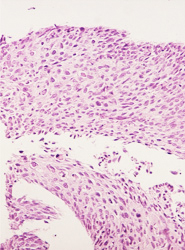

• Lesion de alto grado, con anisocitosis y anisocariosis severas, perdida de la cohesividad y orientacion celular.